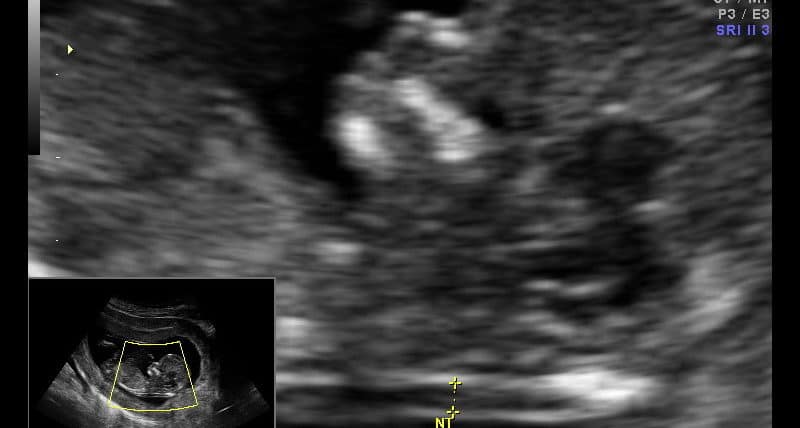

Trabalho do realizado no King's College que correlaciona a concentração sérica materna do fator de crescimento plancentário (PIGF) com aneupolidias.…